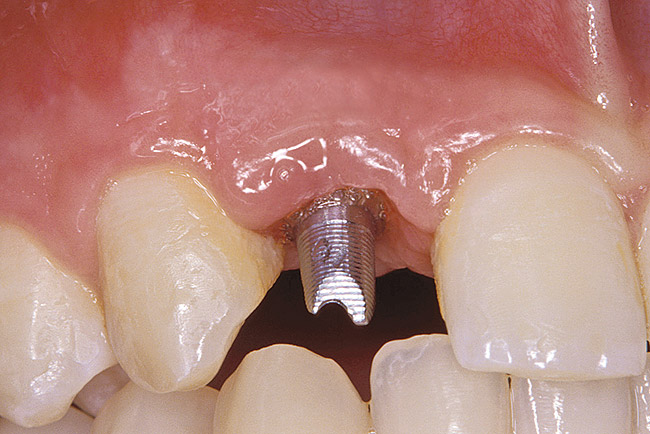

Figure 33  VIRTUAL PLANNING AND SURGERY After the osteotomies were completed, the implants were placed.

Figure 33

Figure 34  VIRTUAL PLANNING AND SURGERY After the osteotomies were completed, the implants were placed.

Figure 34

The 3.7-mm diameter Tapered Screw-Vent implant drilling sequence requires three drills: pilot, intermediate, and final sizing. Thus, three separate templates were fabricated to accommodate these sizes. The templates were removed easily and replaced with the next sequential size in less time than it takes to change the drill on the surgical handpiece. After the osteotomies had been completed, the implants were delivered to the site (Figure 33 and Figure 34). For this internal hex connection implant, the author recommends that the flat of the anti-rotational hex be positioned to the facial for proper orientation of the restorative components (Figure 35). Pre-prepared margins were created from a milled titanium fixture mount transfer post, which was delivered to the implant as support for an immediate transitional restoration. The facial “dot” helped to confirm the orientation of the abutment to the facially positioned flat side of the internal hex connection (Figure 36). Before cementation of the transitional acrylic restorations, a closed-tray, fixture-level impression was made, and a soft-tissue model was fabricated.